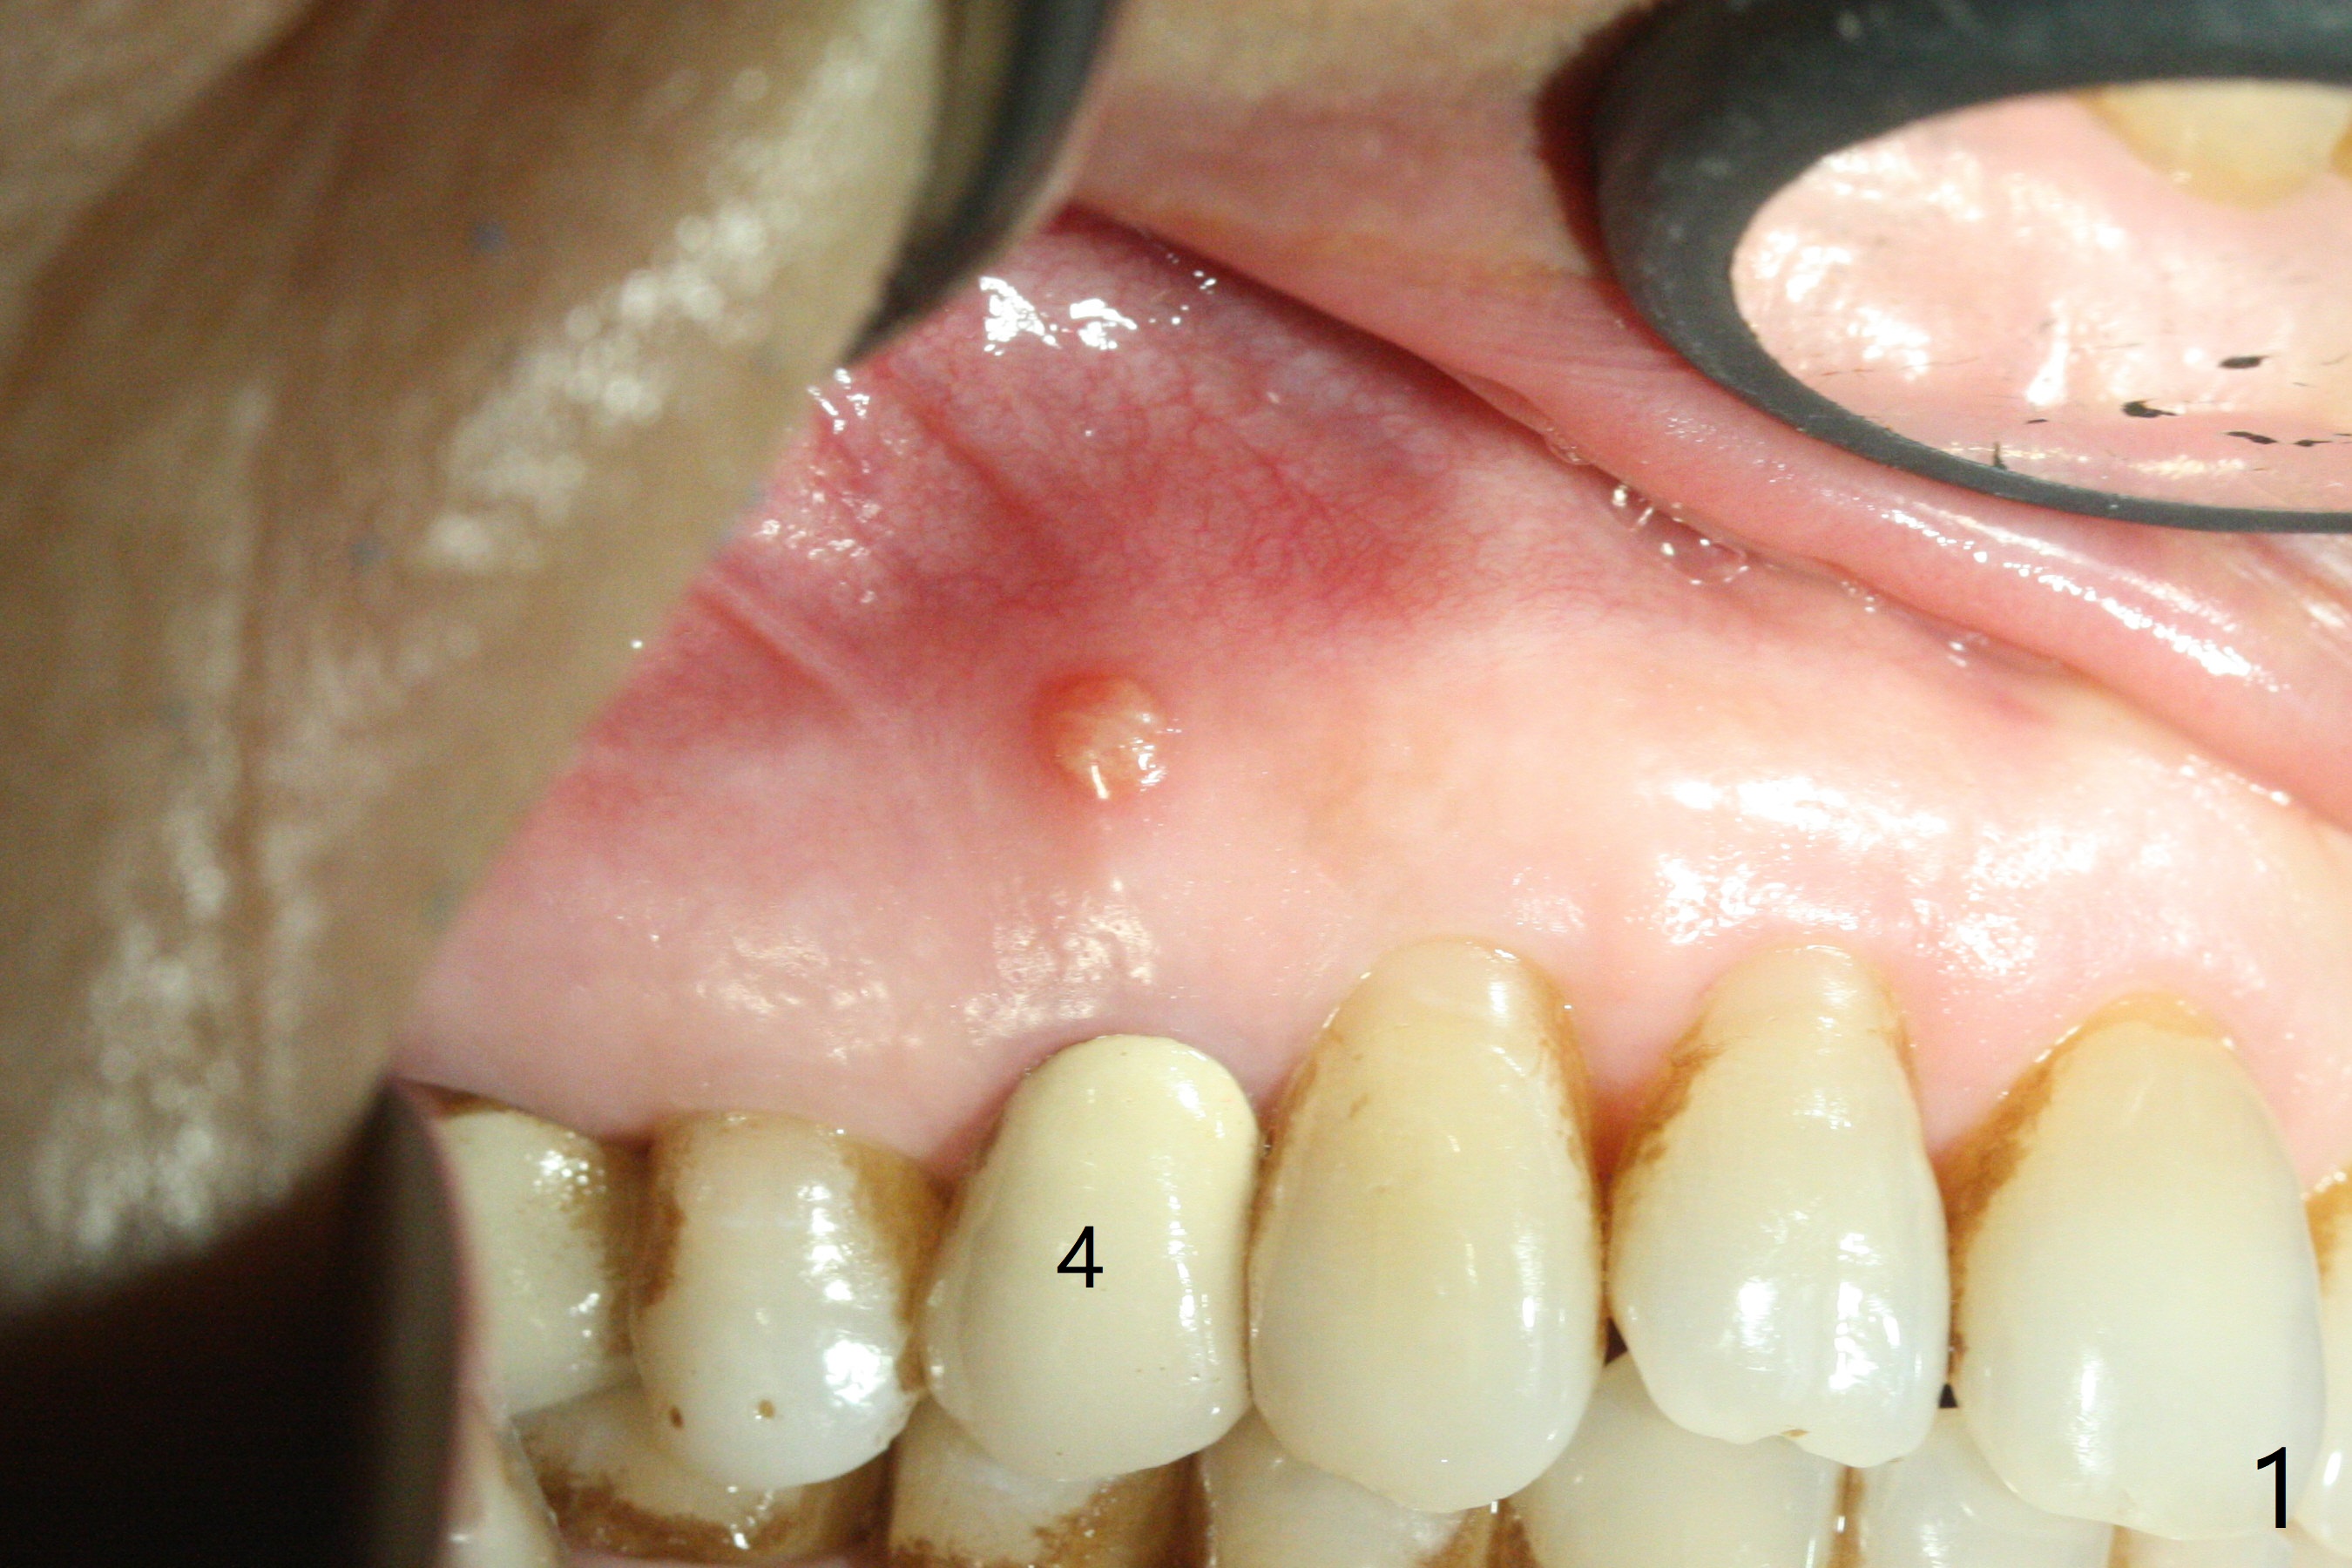

After extraction of the tooth #4 with fistula (Fig.1), the buccal bony defect is superior to the fistula. Before placement of a 4.5x17 mm tissue-level implant (Fig.2) and after osteotomy for bone-level one, PRF and mixture of autogenous bone and allograft are pushed from the socket through the buccal defect for repair (Fig.3 arrowheads). The trajectory of the implant (Fig.4) is consistent with design (Fig.5). The fistula reduces in size and in redness, while the apical elevation (as related to the underlying bone graft) remains prominent 13 days postop (Fig.6,7 *). The distal defect has been apparently repaired 9 months postop (Fig.8 *, as compared to immediately post bone graft in Fig.2). The distal defect has been apparently repaired 9 months postop (Fig.8 *, as compared to immediately post bone graft in Fig.2). The fistula disappears (Fig.9).